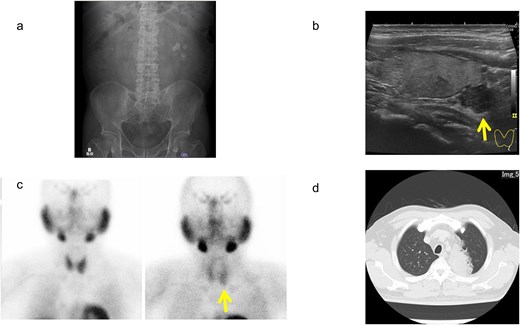

A man in his 50s presented to our hospital with a 1-month history of left lumbar back pain. He had a smoking history of 40 cigarettes per day from age 20 until the time of his hospital visit. He had no history of pancreatic tumors and no specific family history. Kidney–ureter–bladder radiography and computed tomography (CT) revealed a left ureteral calculus (23 mm × 17 mm) and a right renal calculus (Fig. 1a). Blood tests showed hypercalcemia (11.0 mg/dL; normal range: 8.8–10.1 mg/dL) and elevated intact-parathyroid hormone (PTH) (202 pg/mL; normal range: 10–65 pg/mL) levels. The urinary calcium-to-creatinine (Ca/Cre) ratio was elevated at 0.3. Cervical ultrasonography showed a well-defined adenoma in the left inferior thyroid, measuring 18 mm × 12 mm, and we consulted with the Department of Endocrinology and Metabolism (Fig. 1b). 99mTc-methoxy isobutyl isonitrile scintigraphy showed accumulation at the same site during the delayed phase, and a parathyroid tumor was suspected (Fig. 1c).

Imaging findings of urinary calculus, as well as parathyroid and lung lesions. (a) Kidney–ureter–bladder radiograph. (b) Ultrasonography of the cervix. (c) 99mTc-methoxy isobutyl isonitrile scintigraphy. (d) Chest computed tomography. Arrows indicate tumor areas.

Considering the benign parathyroid tumor, we decided to prioritize treatment for the ureteral stone, which was causing mild renal hypofunction and pain. The patient opted to undergo ureteroscopy (URS) owing to the difficulty of living with a nephrostomy. A total of URS procedures were performed on the right and left sides, resulting in the resolution of the ureteral calculi. Stone analysis revealed a composition of >98% calcium oxalate. Two months following the completion of stone treatment, the patient underwent a left inferior parathyroidectomy. Pathological examination confirmed a diagnosis of parathyroid carcinoma, based on findings of extracapsular invasion, despite a Ki67 index of ⁓3% (Fig. 2). As part of a thorough examination of the parathyroid gland, a CT scan of the parathyroid gland revealed a lung tumor (Fig. 1d). A biopsy was performed using endobronchial ultrasound, with findings suggestive of invasive mucinous adenocarcinoma. Additional positron emission tomography-CT showed mild accumulation in the left upper lobe, with no findings indicative of metastasis to the mediastinal or hilar lymph nodes. Four months after completion of stone treatment, a left lobectomy with mediastinal and hilar lymph node dissection was performed. The patient was diagnosed with invasive mucinous adenocarcinoma, staged as pT4N0M0 (Fig. 3). Based on the pathological findings, the patient was diagnosed with synchronous cancers involving localized parathyroid carcinoma and pT4N0M0 stage IIIA invasive mucinous adenocarcinoma. Following parathyroidectomy, the urinary Ca/Cre ratio improved, and blood calcium and intact-PTH levels normalized within the standard range. His lung cancer was treated with four courses of postoperative chemotherapy using cisplatin and vinorelbine, followed by additional courses of maintenance therapy with atezolizumab. Two and a half years have passed since the initial diagnosis. No recurrences of urinary calculus, parathyroid carcinoma, or lung cancer have been observed.